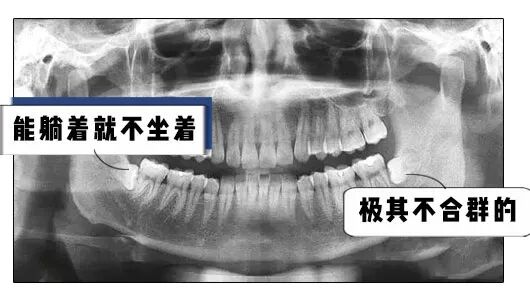

可是一般人的智齿都是这样长的

这样长的

甚至还有这样长的

各种奇形怪状